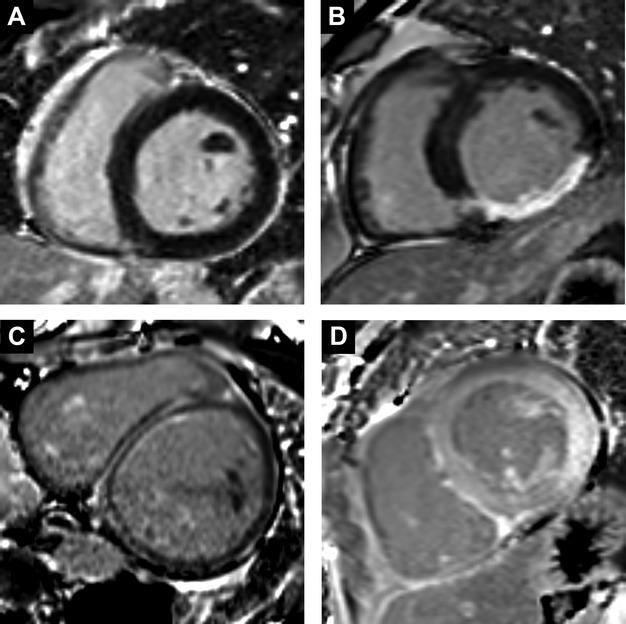

Hospitalization for heart failure (HHF) is among the most important problems confronting medicine. Late gadolinium enhancement (LGE) cardiovascular magnetic resonance (CMR) robustly identifies intrinsic myocardial damage. LGE may indicate inherent vulnerability to HHF, regardless of etiology, across the spectrum of heart failure stage or left ventricular ejection fraction (LVEF).

The presence and extent of LGE is associated with vulnerability for HHF, including higher risks of HHF across the spectrum of heart failure stage and LVEF. Even when LVEF is severely decreased, those without LGE appear to fare reasonably well. LGE may enhance risk stratification for HHF and may enhance both clinical and research efforts to reduce HHF through targeted treatment.